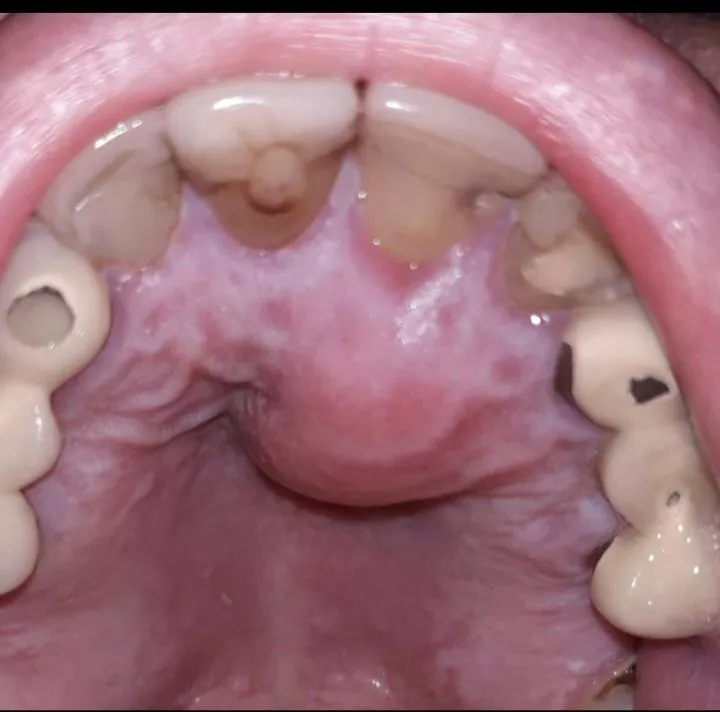

Abscess roof of mouth followed root canal nudes